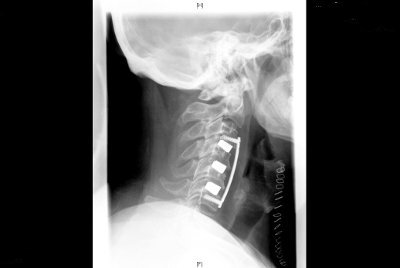

Columna cervical

• Tratamiento quirúrgico de la Hernia Discal Cervical (prótesis rígidas y móviles).